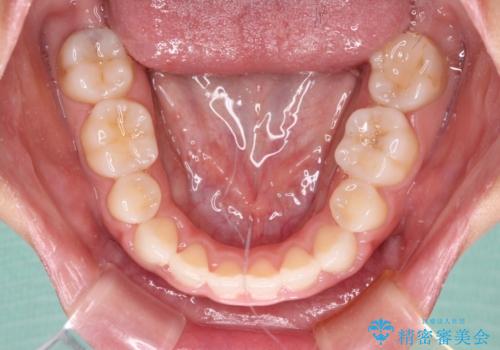

- 口元の突出感を気にして来院された患者様です。

上下左右の第一小臼歯4本を抜歯して口元を下げる治療計画としました。

表側のワイヤー矯正に比べると治療期間は長く、費用も高額となりますが、どうしても目立たせたくないという方にはお勧めの抜歯矯正です。